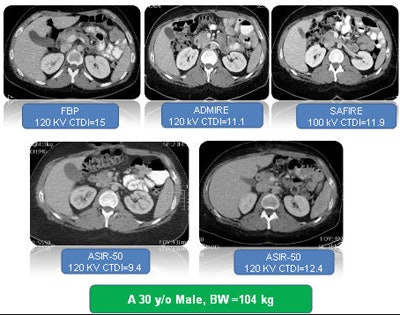

Radiologists face big challenges in applying iterative reconstruction techniques from different vendors, said Dr. Dushyant Sahani from Massachusetts General Hospital (MGH), a large teaching hospital that is part of a network that employs multiple CT scanner models in far-flung locations. Fortunately, image quality differences between scans reconstructed on different equipment using different IR techniques can be minimized by matching objective noise using techniques the group has developed, he said.

"The biggest question is, when you have so much diversity ... how do we provide images that are ... not too dissimilar?" he said. "They shouldn't look so different that comparison becomes difficult when you want to match up the images between filtered back projection as well as with various reconstruction techniques, because it creates challenges for the radiologists to interpret."

Image quality improvement has several components, of which objective noise and edge preservation are especially important, he said. Noise can be modified with the variable strength settings in each iterative reconstruction technique, as follows:

To test the variability of noise reduction in different protocols, the group scanned a phantom using mAs levels from 25 to 100, with a fixed kVp of 120. The images were reconstructed at various IR strengths and reconstruction techniques to understand the magnitude of noise reduction with each technique, Sahani said.

"What we noticed first is that there is a nonlinear drop in image noise as soon as you increase the amount of image reconstruction," he said. "Moreover, the maximum amount of noise improvement one can get is about 50%. The point is that if you drop your radiation dose by 80%, the maximum noise improvement that one can get from the statistical reconstruction technique is only 50%. So it might not work if one desires an excessive amount of dose reduction."

The experiment with phantoms also showed that achieving an approximate 30% noise reduction at 120 kVp in ASIR means setting the strength to 50, he said. For the same job, iDose is set at level 4 and SAFIRE at level 3.